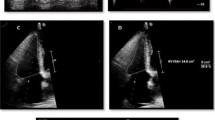

Transthoracic echocardiography

As reported previously [11, 12] image acquisition and analysis was undertaken by 2 experienced, accredited sonographers using an iE 33 system with S5-1 transducer (Philips Medical Systems, Best, The Netherlands). Echocardiography was performed primarily to confirm preserved LVEF for study inclusion and E/E′ was also calculated to assess LV filling pressure.